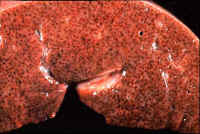

Fig.10-2-2 Centrolobulr necrosis in acute right

heart failure. Gross changes

Cut surface of a liver with acute passive congestion. The lobular markings are accentuated. The small lobulescan be easily identified because of congestion of

centrolobular veins which appear as small red dots.